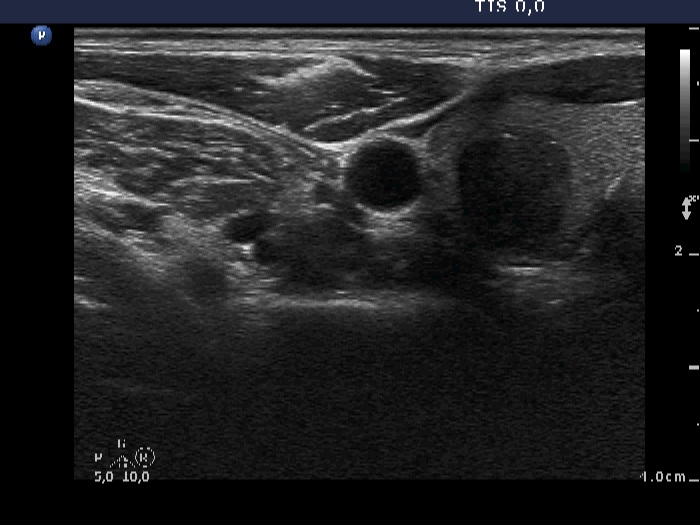

Ultrasonography. The thyroid was echonormal. There was a spongiform-type cyst in the right lobe. The small cystic areas of the lesion exhibited posterior back wall enhancement. The vascularization was scanty. Compared with the former examination, the nodule remained just as large. There was another nodule in the left lobe which was not described on previous ultrasound report. This lesion was hypoechogenic, presented hyperechogenic granules and showed taller-than-wide sign.

Comment. Note the typical presentation of posterior back wall enhancement.